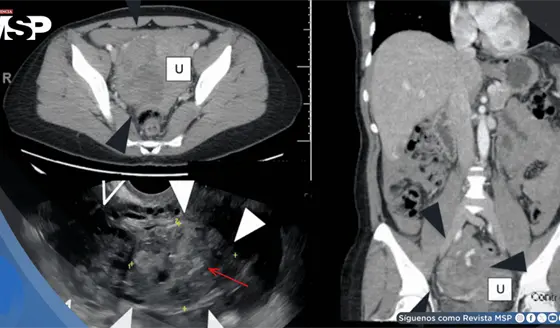

Rotura ovárica por embarazo ectópico fue confundida con cáncer en una mujer con ascitis y masa abdominal